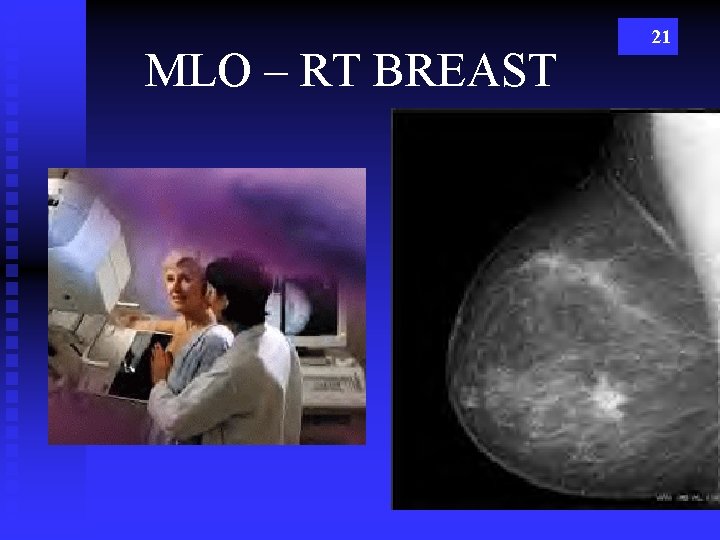

MLO – RT BREAST 21